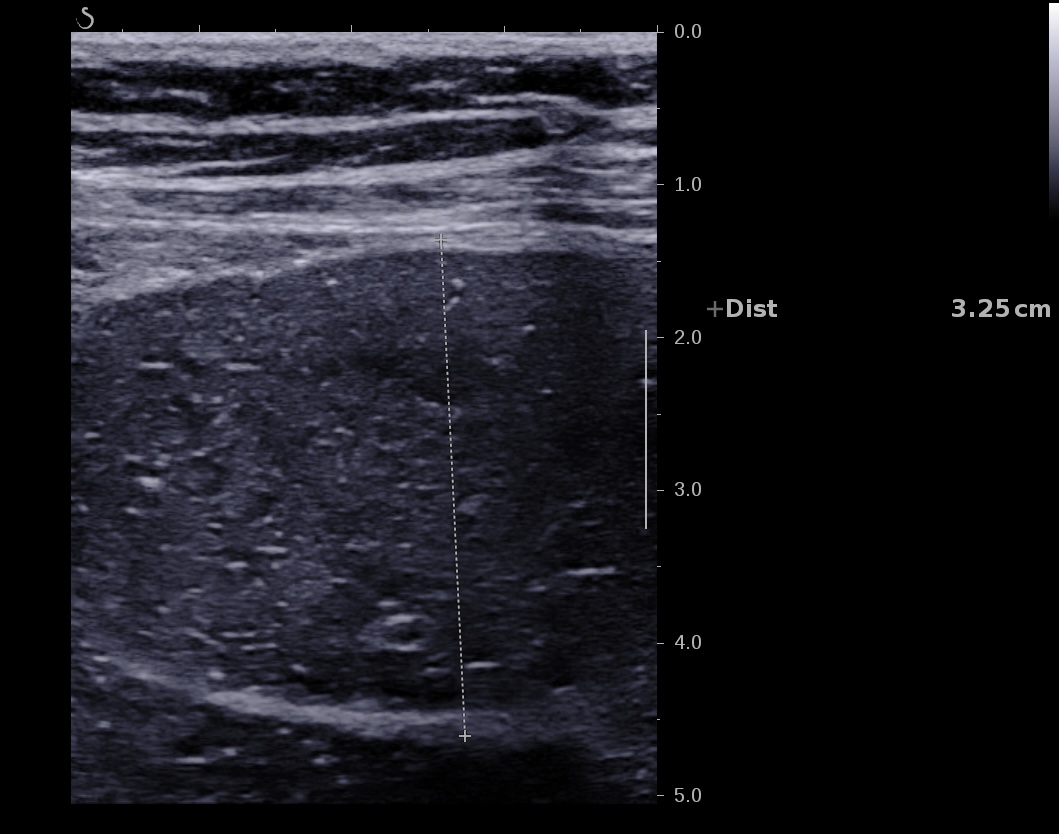

L'occlusion du grêle est très facile à voir en échographie

On peut voir en cas d'occlusion:

Sténose serrée